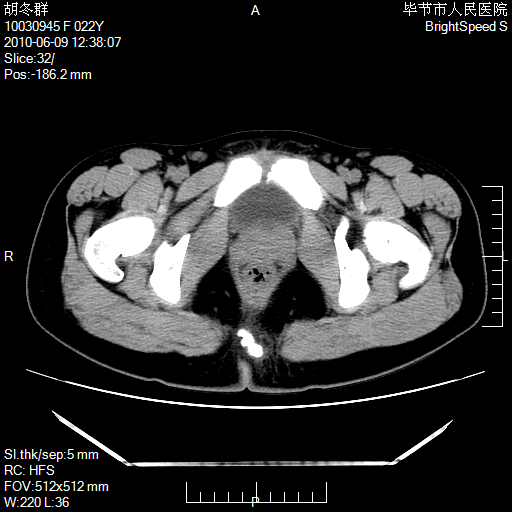

患者23岁,发现腹部包块3月。

左侧卵巢囊腺瘤或囊腺癌

盆腔内囊性占位性病变;考虑左侧卵巢囊腺瘤。

有分隔、壁薄,支持考虑左侧卵巢囊腺瘤。

左侧卵巢浆液性囊腺瘤。

支持考虑左侧卵巢囊腺瘤;宫腔积液。

有分隔、壁薄,支持考虑左侧卵巢囊腺瘤。排尿后,膀胱缩小,由于重力作用,肿块下移就到了膀胱位置,很好理解。